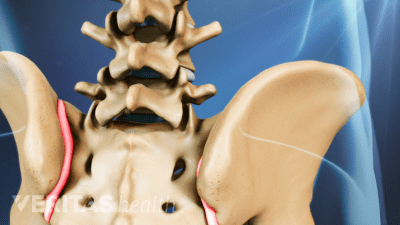

Discover the best radiographic tests for diagnosing SI joint dysfunction and ruling out serious medical conditions.